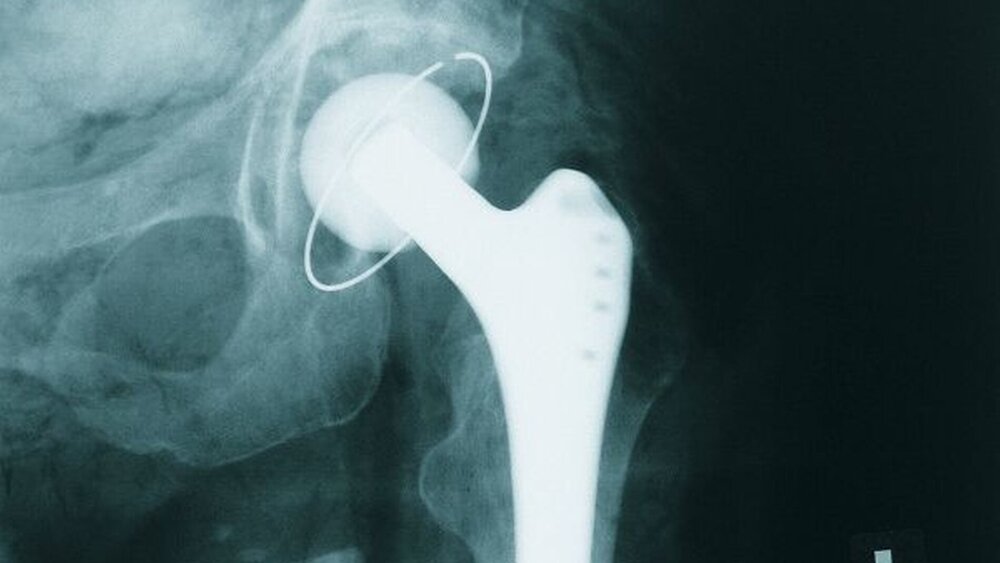

Manchmal sind die mit Identifizierungen betrauten Personen vor beinahe unlösbare Aufgaben gestellt: wenn keine ante-mortalen primären Identifizierungsmerkmale (Daktyloskopie, DNA, Zähne) zur Verfügung stehen. Dass in diesen mutmaßlich aussichtslosen Fällen dennoch Möglichkeiten einer positiven Identifizierung beziehungsweise eines Identifizierungsausschlusses bestehen, verdeutlichte Dr. Dr. Claus Grundmann, Duisburg, mithilfe seines Vortrags zur „Bedeutung sekundärer Identifizierungsmerkmale – insbesondere beim Fehlen primärer Identifizierungsmerkmale“: Zu den eher „weicheren“ sekundären Identifizierungsmerkmalen zählt man Körpergröße, Körpergewicht, Haarlänge, Haarfarbe, Augenfarbe, Ohrform, Bartwuchs, Bekleidung, Ketten, Uhren und mehr, denen in der Regel nur „additive“ Bedeutung beizumessen ist. Ein wenig mehr Bedeutung im Identifizierungsprozess haben „Standard“-Narben (Schilddrüse, Gallenblase, Appendix, Leistenbruch), „einfache“ Tätowierungen, „typische“ Hautperforationen wie Piercings und sogenannte Tunnel, intrauterine Spiralen und mehr. Von weitaus höherer Aussagekraft sind individuelle Narben (insbesondere nach Unfällen oder Verbrennungen), einoder beidseitige Lippen-Kiefer-Gaumenspalten, Stents in Herzkranzgefäßen, Amputationen von Gliedmaßen, Ringe mit Individualgravuren und vieles mehr. Zu den körperlichen Merkmalen, die ähnliche Bedeutung wie die primären Identifizierungsmerkmale (Daktyloskopie, DNA, Zähne) haben, zählt man – meist mit Individualnummern versehene – Herzschrittmacher, Defibrillatoren, Herzklappenersatz, künstliche Hüft- und Kniegelenke, Ventile zur Ableitung eines Hydocephalus internus, Aneuryma- Clips an den Gefäßen der Hirnbasis, Glasaugen, Brustimplantate sowie aufwendige und hochindividuelle Tätowierungen – oftmals sogar mit diversen Namen versehen.